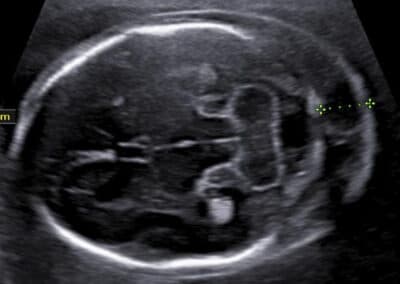

Chybějící nosní kůstka, která patří ke znakům Downova syndromu I dalších genetických vad

Šíjový edém, který patří ke znakům genetických vad

Echogenní fokus v srdíčku miminka, který patří k vyšetřovaným znakům Downova syndromu

Určíme uložení a stav placenty, množství plodové vody a počet cév v pupečníku. Změříme velikost příčného průměru a obvodu hlavičky, obvod bříška a délku stehenní kosti miminka a určíme jeho hmotnost. Vyšetříme také podrobně všechny jeho orgány, hledáme přitom nejen orgánové vady, ale i malých odchylky normálního vzhledu, tzv. markery genetických vad. Pokud si budete přát znát pohlaví miminka, rádi vám jej sdělíme. Při vyšetření mozku miminka, případně lebky a dalších orgánů si pomáháme ke zpřesnění vyšetření i využitím 3D ultrazvuku. Budete-li si přát připojit 3D-4D ultrazvukové vyšetření s reálným zobrazením vzhledu obličeje vašeho miminka , rádi jej také připojíme.